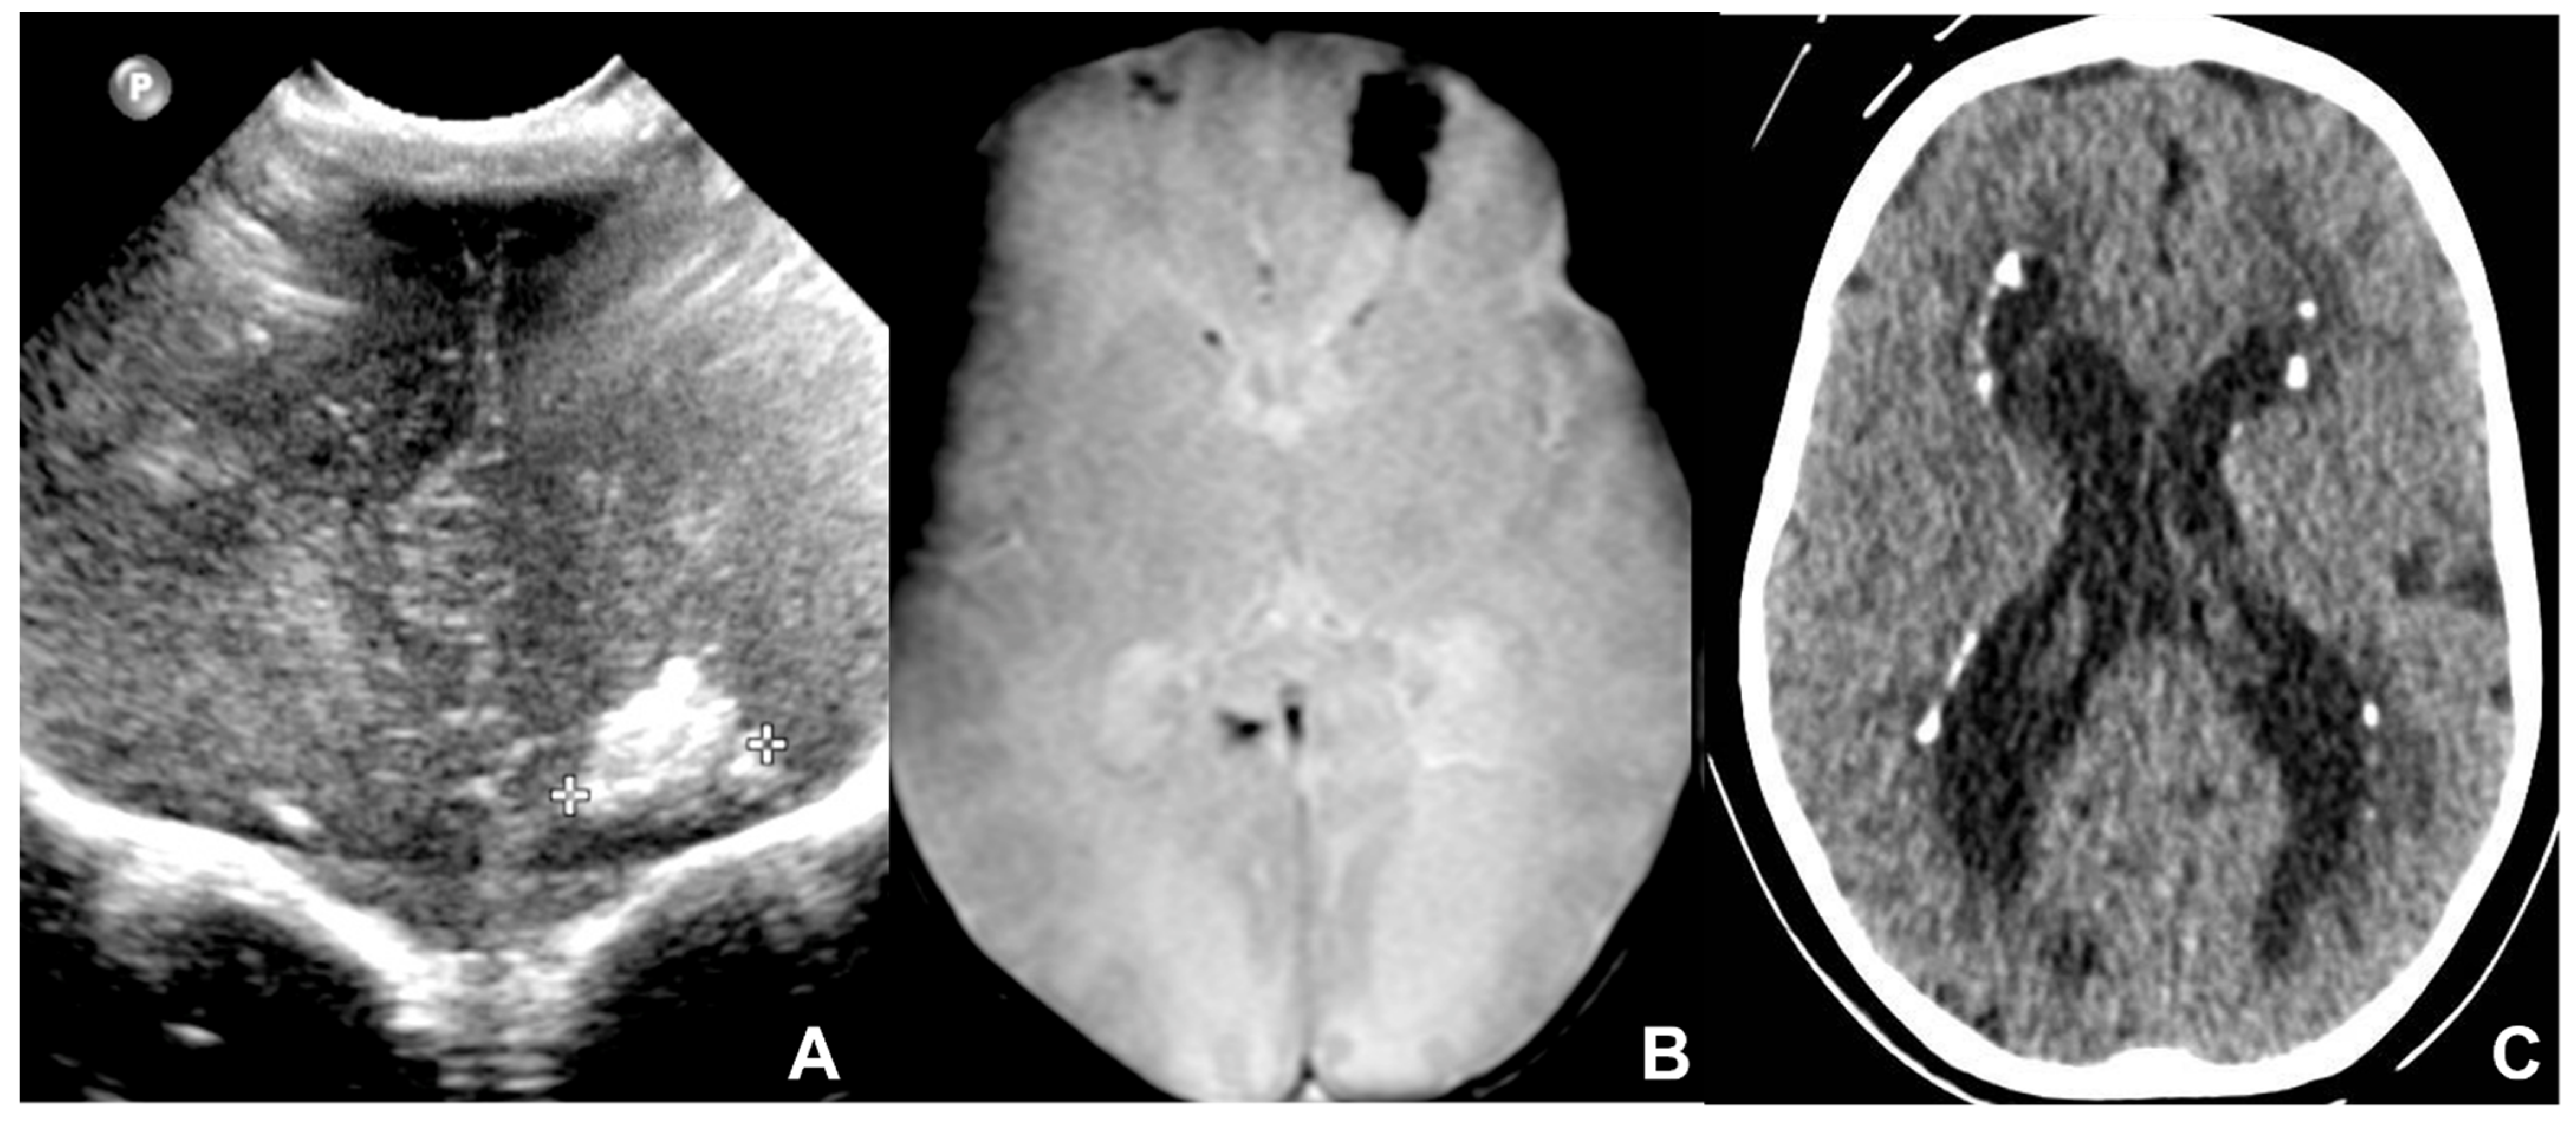

2.2. Toxoplasmosis

- Diebler, C.; Dusser, A.; Dulac, O. Congenital toxoplasmosis. Clinical and neuroradiological evaluation of the cerebral lesions. Neuroradiology 1985, 27, 125–130. [Google Scholar] [CrossRef]

- Jacquemard F Ultrasonographic signs of congenital toxoplasmosis. Arch. Pediatr. 2003, 10 (Suppl. S1), 35–38.

- Lago, E.; Baldisserotto, M.; Filho, J.H.; Santiago, D.; Jungblut, R. Agreement between ultrasonography and computed tomography in detecting intracranial calcifications in congenital toxoplasmosis. Clin. Radiol. 2007, 62, 1004–1011. [Google Scholar] [CrossRef] [PubMed]

- Epelman, M.; Daneman, A.; Blaser, S.I.; Ortiz-Neira, C.; Konen, O.; Jarrín, J.; Navarro, O.M. Differential diagnosis of intracranial cystic lesions at head US: Correlation with CT and MR imaging. Radiographics 2006, 26, 173–196. [Google Scholar] [CrossRef]

- Beltinger, C.; Saule, H. Sonography of subependymal cysts in congenital rubella syndrome. Eur. J. Pediatr. 1988, 148, 206–207. [Google Scholar] [CrossRef]

- Yamashita, Y.; Matsuishi, T.; Murakami, Y.; Shoji, H.; Hashimoto, T.; Utsunomiya, H.; Araki, H. Neuroimaging findings (ultrasonography, CT, MRI) in 3 infants with congenital rubella syndrome. Pediatr. Radiol. 1991, 21, 547–549. [Google Scholar] [CrossRef]